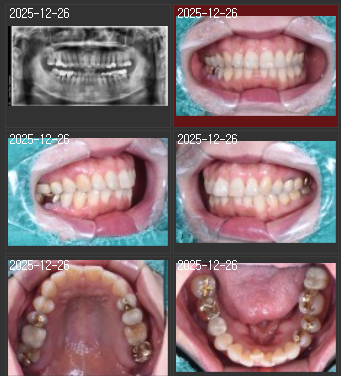

검단가온치과에서는 초진 시 전문 DSLR 장비로 전체 치아를 5-10장 촬영합니다.

정면, 좌우 측면, 상악, 하악을 포함한 다각도 촬영을 통해 구강 상태를 종합적으로 기록합니다.

촬영한 사진은 큰 모니터에서 환자와 함께 확대하며 살펴볼 수 있어 치료 필요 부위를 명확하게 이해할 수 있습니다.